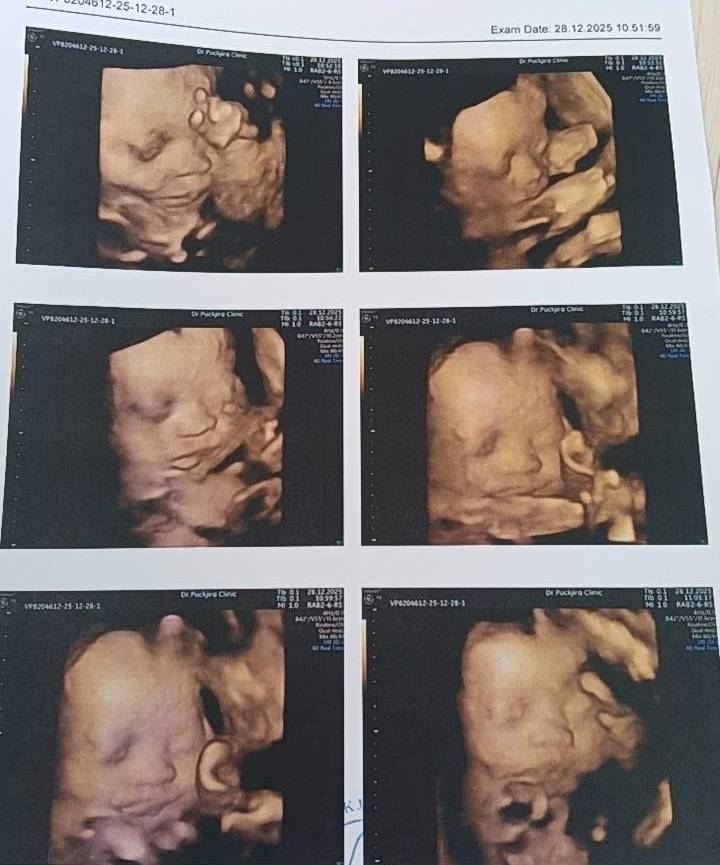

喜報!1月28日四維檢查順利通關。胎兒發育無異常,恭喜喜獲健康男寶,圓滿達成心願

1月15日完成四維排畸檢查,

結果顯示未見異常,各項發育指標正常。

階段性檢查順利通過,母嬰狀態良好,

感謝關心,繼續穩穩前行,期待相見。